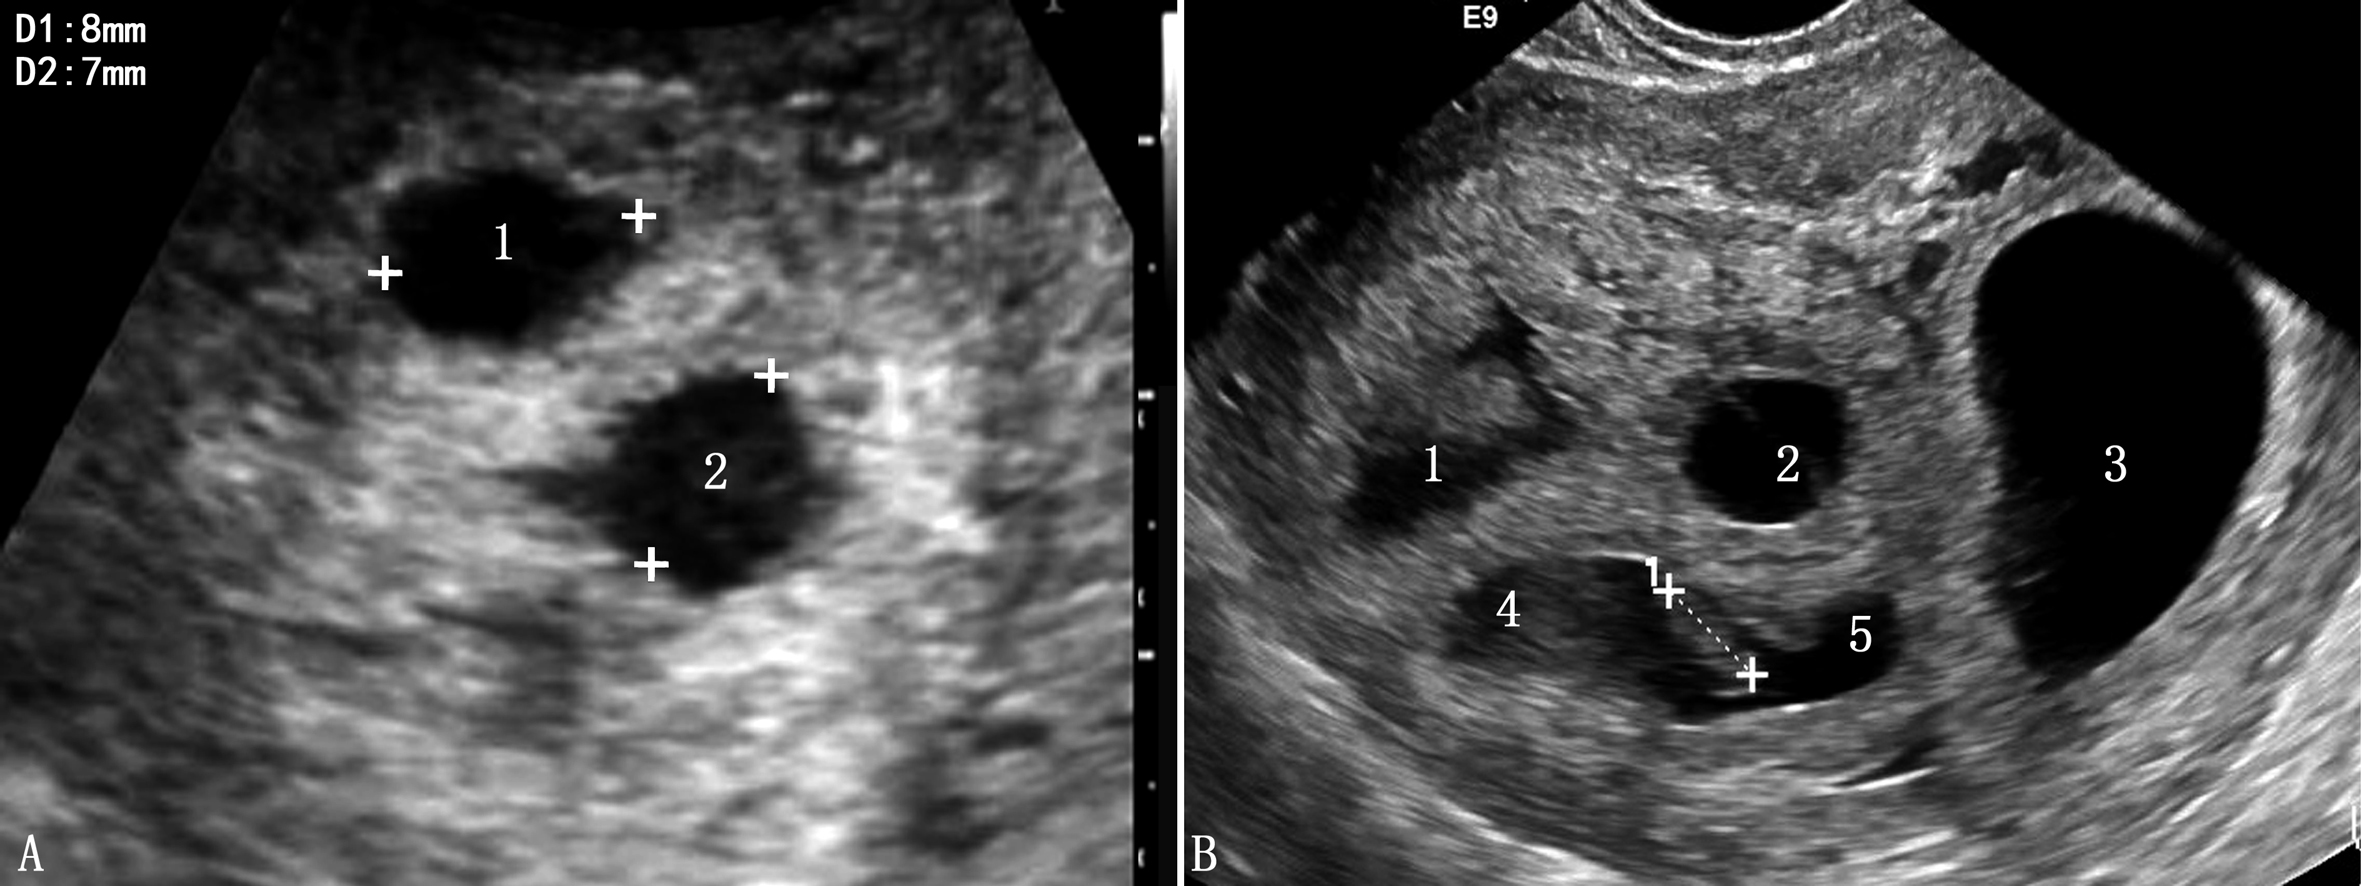

1.妊娠囊 妊娠囊的计数是早期诊断多胎妊娠的基础。早期妊娠超声显像检查妊娠囊回声及其评价方法可采用同单胎妊娠。TAU于停经后第6周或TVU于第5孕周即可显示妊娠囊(图1A)。需要注意的是早期妊娠显示的单胎妊娠或多胎妊娠可能会有一定的误差,有报道在孕6周以前有11%(24/213)的双绒毛膜囊双胎妊娠和86%(6/7)的单绒毛膜囊双胎妊娠被诊断为单胎妊娠。

超声检查显示的分离的妊娠囊个数即为绒毛膜囊个数(图1B),两个妊娠囊则提示双绒毛膜囊双胎妊娠,三个妊娠囊即提示三个绒毛膜腔。停经10周时羊膜腔扩大、绒毛膜逐渐变薄,羊膜与绒毛膜融合,超声显像检查对绒毛膜特性评估的难度明显增加。

图1多胎妊娠声像图 A:TVU显示两个孕囊 B:TVU显示5个孕囊